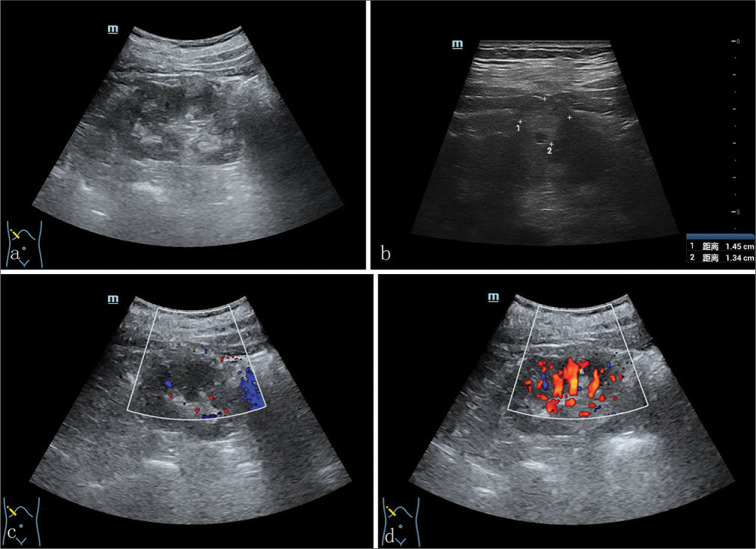

我们报告了一例 71 岁男性肾小管囊性细胞癌(TRCC)患者的病例,这是一种罕见的肾肿瘤。患者因体检时发现右肾中极有一个囊性结节,经泌尿科超声检查后入院。该结节在常规超声检查中呈高回声,在对比增强超声检查中,增厚的囊壁在峰值相的增强强度与肾实质相似。计算机断层扫描血管造影显示肿瘤呈异质性对比增强,磁共振成像显示 T1 加权成像(WI)呈低密度,T2WI 呈高密度。组织学上,海绵表面由典型的管状和多房囊性成分组成,内衬单层上皮细胞。最终病理诊断为 TRCC。患者顺利地接受了腹腔镜右肾根治术。患者出院后随访 12 个月,未发现局部或远处转移迹象。总之,TRCC 应根据放射学和组织学的综合结果进行准确诊断,以确保及时手术和更好的预后。

We present a case involving a 71-year-old male with tubulocystic renal cell carcinoma (TRCC), which is a rare entity of renal neoplasm. The patient was admitted for a cystic nodule on the middle pole of the right kidney by urological ultrasound during physical examination. The nodule presented with hyperechoic on conventional ultrasonic and the enhancing intensity of thicken cystic wall at the peak phase in contrast-enhanced ultrasound was similar to that of the renal parenchyma. Findings from computed tomography angiography exhibited heterogeneously contrast enhancing tumor, and magnetic resonance imaging demonstrated hypointense on T1-weighted images (WI) and hyperintense on T2WI. Histologically, the spongy surface was composed of the typical tubular and multiloculated cystic components lined by a single layer of epithelial cells. The final pathological diagnosis was TRCC. The uneventful laparoscopic right radical nephrectomy was conducted. The patient was followed up for 12 months after discharge and no signs of local or distant metastasis were found. In conclusion, TRCC should be accurately diagnosed on the basis of comprehensive radiological and histological findings to ensure a timely surgery and better prognosis.